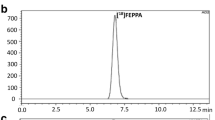

Utilizing a bis(thiosemicarbazone) backbone, a fluorescent ATSM-FITC conjugate was synthesized. Its copper complex, Cu(ATSM-FITC) was thoroughly tested as a biosensor for H2S. The same ATSM-FITC ligand was quantitatively labeled with [64Cu]CuCl2 to obtain a radioactive [64Cu][Cu(ATSM-FITC)] imaging probe. Biodistribution and positron emission tomography (PET) imaging studies were performed in healthy mice and neuroinflammation models.

The Cu(ATSM-FITC) complex reacts instantly with H2S to release CuS and becomes fluorescent. It showed excellent reactivity, sensitivity, and selectivity to H2S. Endogenous H2S levels in living cells were successfully detected by fluorescence microscopy. Exceptionally high brain uptake of [64Cu][Cu(ATSM-FITC)] (> 9% ID/g) was observed in biodistribution and PET imaging studies. Subtle changes in brain H2S concentrations in live mice were accurately detected by quantitative PET imaging. Due to its dual modality feature, increased H2S levels in neuroinflammation models were characterized at the subcellular level by fluorescence imaging and at the whole-body scale by PET imaging.